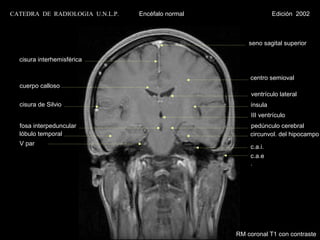

CATEDRA DE RADIOLOGIA U.N.L.P.   Encéfalo normal                Edición 2002

seno sagital superior

cisura interhemisférica

centro semioval

cuerpo calloso

ventrículo lateral

cisura de Silvio                                     ínsula

III ventrículo

fosa interpeduncular                                 pedúnculo cerebral

lóbulo temporal                                      circunvol. del hipocampo

V par

c.a.i.

c.a.e

.

RM coronal T1 con contraste